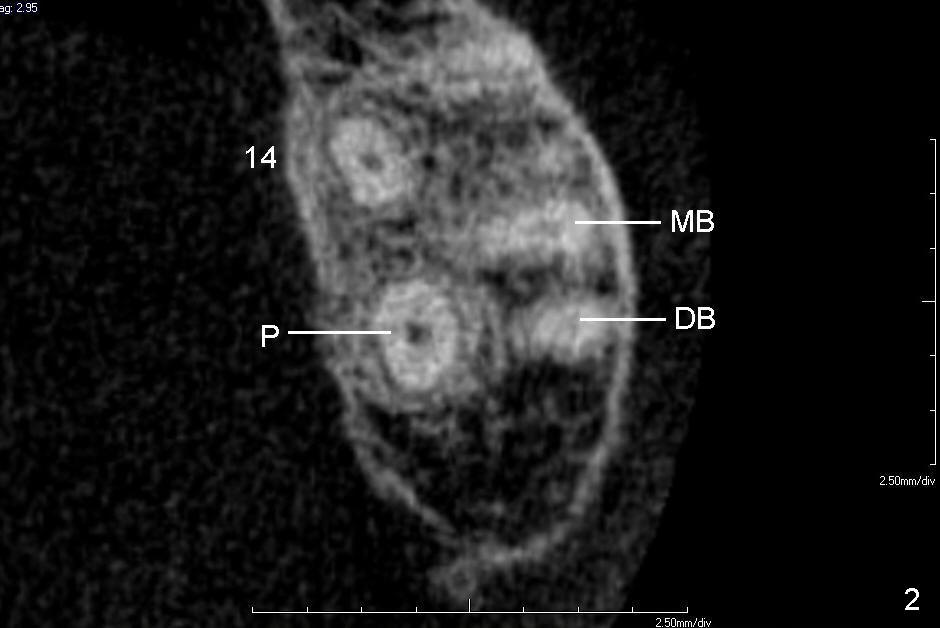

A 60-year-old man requests replacing the teeth #2 and 3, which have root fracture. Both of these two teeth have 3 roots (palatal (P), mesiobuccal (MB) and distobuccal (DB) (X-ray not shown). CT images from a different patient are used instead (Fig.1-3). The upper left image of Fig.1 (i.e., Fig.2) is an axial section, lower left (Fig.3) coronal and lower right sagittal.